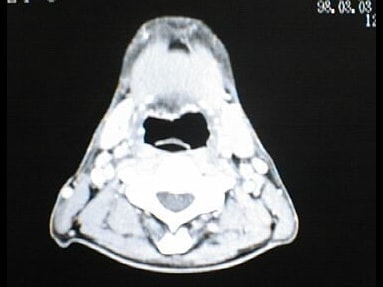

中咽頭末期がん消滅CT画像②

入院3か月後癌消滅CT画像②

中咽頭末期がんCT画像③

入院当時CT画像③

中咽頭末期がん消滅CT画像③

入院3か月後癌消滅CT画像③